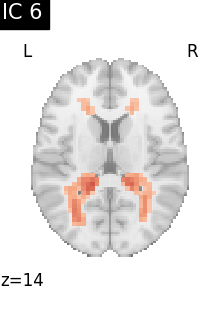

Finally, we plot the map for each ICA component separately

for i, cur_img in enumerate(iter_img(canica_components_img)):

plot_stat_map(

cur_img,

display_mode="z",

title=f"IC {int(i)}",

cut_coords=1,

vmax=0.05,

vmin=-0.05,

colorbar=False,

)

show()